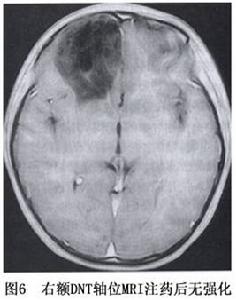

DNT少見,自Daumas-Duport首批報導39例以來,以後均只有零星個例報導腫瘤多見於兒童,但也有青年患者,男女性無明顯差異。DNT好發於幕上,62%~78%位於顳葉,其餘幾乎均位於額葉。有人報導DNT占20歲以下組神經上皮性腫瘤的1.2%全年齡組的0.63%

胚胎髮育不良性神經上皮腫瘤病程長,常在幼年或年輕時發病,主要表現為複雜性的局灶性癲癇發作。癲癇常為頑固性而不易控制。腦電圖常有病灶部位的癲癇波存在。因本病生長緩慢,局部顱骨可受壓變薄。

對於胚胎髮育不良性神經上皮腫瘤手術切除來消滅致病灶是有效方法,手術目的是切除病灶控制癲癇發作可作病灶全切除,或是對發育不良的皮質及部分病灶切除,一般術後癲癇能完全消失,不需術後放療或化療,

胚胎髮育不良性神經上皮腫瘤預後好,很少復發,不影響病人生存。